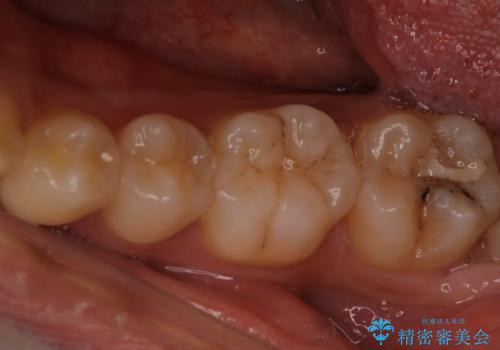

- 検査の結果、虫歯が見つかった患者様です。

白く目立たないものでの治療をご希望されたため、セラミックインレーでの治療となりました。